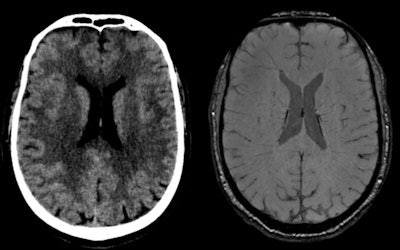

![Traumatic brain injury in 64-year-old male skier who had seizures after trauma (broken helmet, Glasgow Coma Scale [GCS] 9/15), psychomotor agitation). CT (left) shows linear hyperdensity adjacent to septum pellucidum. MRI (right) shows susceptibility artifact compatible with hemorrhagic residue in contact with middle part of septum pellucidum on its right lateral surface above the fornix. All figures courtesy of RSNA 2020 and Dr. Mariana Dalaqua.](https://img.auntminnie.com/files/base/smg/all/image/2020/12/am.2020_12_02_20_47_7196_2020_12_02_winter_sports_figure1.png?auto=format%2Ccompress&fit=max&q=70&w=400)

"CT depicts very clearly facial and skull fractures, as well as extra-axial hemorrhage (epidural, subdural, and subarachnoid bleeding). Brain contusions can also be characterized, especially the hemorrhagic ones, but are usually more obvious only after a few hours, as vasogenic edema becomes more evident," the Sion group pointed out.

A normal CT is one of the factors that define a brain injury as mild. Initial findings representing diffuse axonal injury can be really subtle and should be further investigated with MRI in cases of high kinetic energy trauma with normal CT and clinico-radiological dissociation, they added.